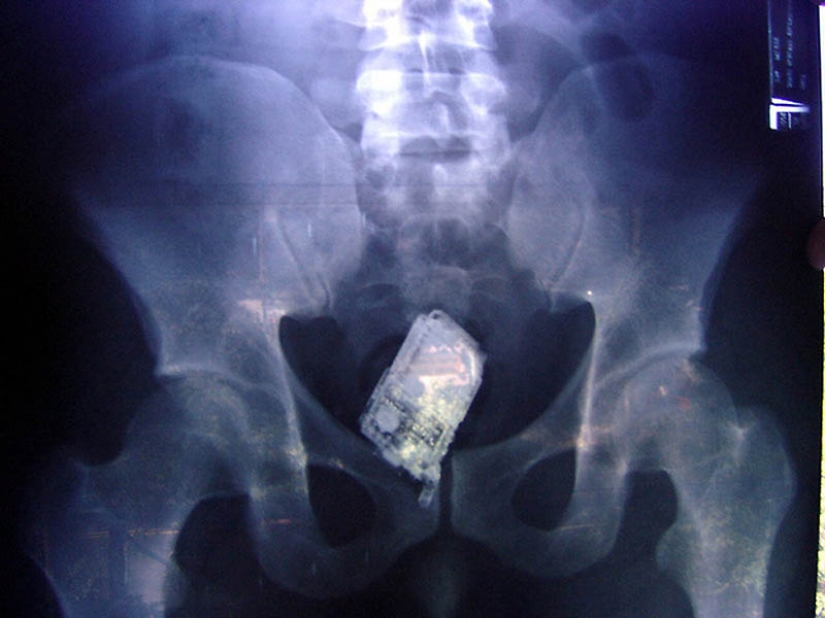

14. Cell in the gut of the prisoner.